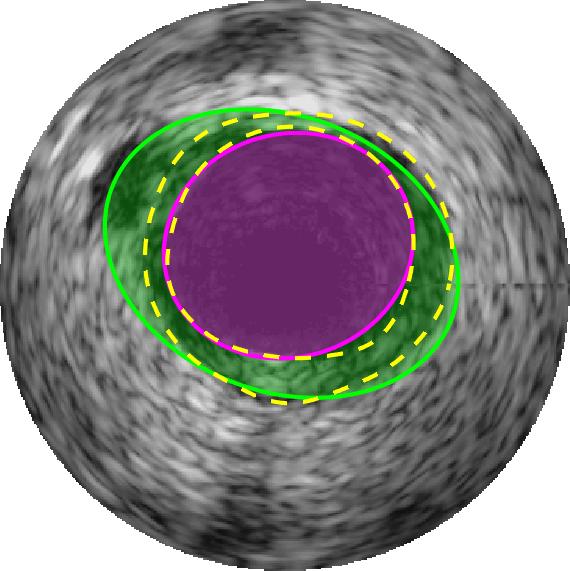

Qualitative evaluations are illustrated in Figure 4 and show the successful segmentation results of the proposed EREL selection strategy for 20 IVUS frames. The lumen areas are highlighted by the magenta colour while the media regions are green. Also, the manually annotated contours for both lumen and media are drawn as yellow dashed lines. As we can see, the chosen frames contain a variety of lumen and media morphologies.